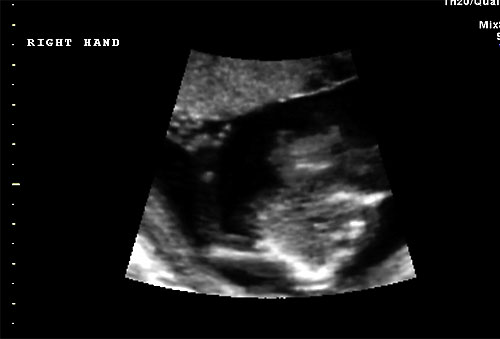

Normal 16 week right hand |